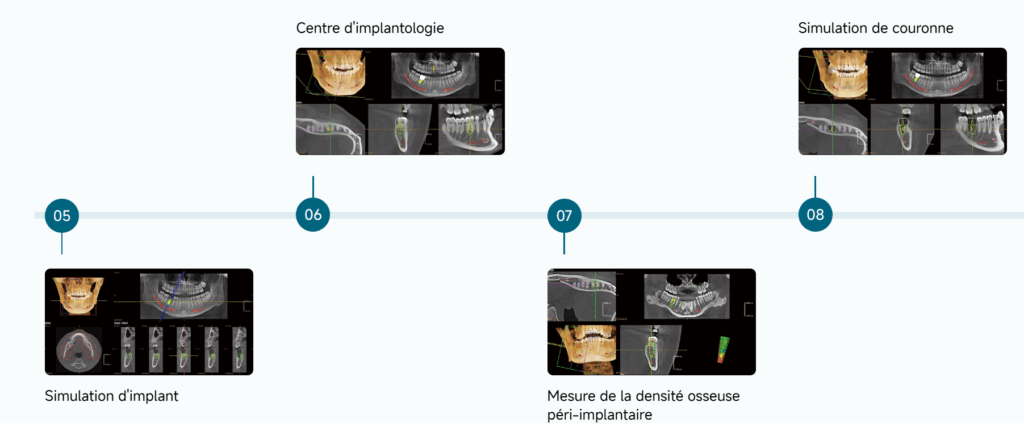

Votre puissant assistant IA

Solution implantaire tout-en-un

L’amélioration de la sécurité et de l’efficacité des interventions chirurgicales d’implants facilite la communication entre le médecin et le patient.